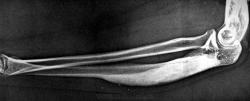

Пол пациента: Мужской пол Тип патологии: Другое Область исследования: Скелетно-мышечная система Методы исследования: Rg Деформация предплечья давно. Болей и других мешающих факторов нет. ID:1068 Sun, 07/02/2010 - 13:59 #1 Ola-la Offline Last seen: 11 months 4 weeks ago Joined: 06.12.2008 - 09:33 Posts: 1786 Ну, если клиники никакой, тогда может это мелореостоз? https://www.instagram.com/pediatricradiology/ Sun, 07/02/2010 - 14:02 #2 Анатолий Владим... Offline Last seen: 7 years 11 months ago Joined: 16.10.2009 - 21:16 Posts: 1941 Уважаемые коллеги! Может еще кто выскажется? Sun, 07/02/2010 - 14:02 #3 stovbav Offline Last seen: 2 years 4 months ago Joined: 20.12.2009 - 17:28 Posts: 7066 Очень похоже на мелореостоз (б-нь Лери)..."...Иногда поводом для обращения к врачу является вторичная деформация пораженного участка скелета....".... Болезни ног: виды, симптомы, причины, профилактика и лечение Sun, 07/02/2010 - 14:15 #4 Анатолий Владим... Offline Last seen: 7 years 11 months ago Joined: 16.10.2009 - 21:16 Posts: 1941 Раз два наших "Старших Офицера" дружно и единогласно выставили мелореостоз - деваться некуда - он, родимый. Монооссальная форма. Sun, 07/02/2010 - 14:18 #5 Ola-la Offline Last seen: 11 months 4 weeks ago Joined: 06.12.2008 - 09:33 Posts: 1786 https://www.instagram.com/pediatricradiology/ Sun, 07/02/2010 - 14:35 #6 stovbav Offline Last seen: 2 years 4 months ago Joined: 20.12.2009 - 17:28 Posts: 7066 .... Болезни ног: виды, симптомы, причины, профилактика и лечение Sun, 07/02/2010 - 14:37 #7 Катенёв Валенти... Offline Last seen: 7 years 2 months ago Joined: 22.03.2008 - 22:15 Posts: 54876 Ольгины "смайлы" - сверх похвал. По всей видимости, она их "питает" специальным продуктом? Sun, 07/02/2010 - 14:56 #8 Ola-la Offline Last seen: 11 months 4 weeks ago Joined: 06.12.2008 - 09:33 Posts: 1786 Ага, это я дополнение к Firefox установила, там куча смайликов https://www.instagram.com/pediatricradiology/ Sun, 07/02/2010 - 14:59 #9 stovbav Offline Last seen: 2 years 4 months ago Joined: 20.12.2009 - 17:28 Posts: 7066 Ola-la wrote: Ага, это я дополнение к Firefox установила, там куча смайликов Прикольно...теперь все время из окна дразниться будете?... Болезни ног: виды, симптомы, причины, профилактика и лечение Sun, 07/02/2010 - 15:04 #10 Ola-la Offline Last seen: 11 months 4 weeks ago Joined: 06.12.2008 - 09:33 Posts: 1786 Нет, только изредка https://www.instagram.com/pediatricradiology/

Ну, если клиники никакой, тогда может это мелореостоз?

Очень похоже на мелореостоз (б-нь Лери)..."...Иногда поводом для обращения к врачу является вторичная деформация пораженного участка скелета...."....

Раз два наших "Старших Офицера" дружно и единогласно выставили мелореостоз - деваться некуда - он, родимый. Монооссальная форма.